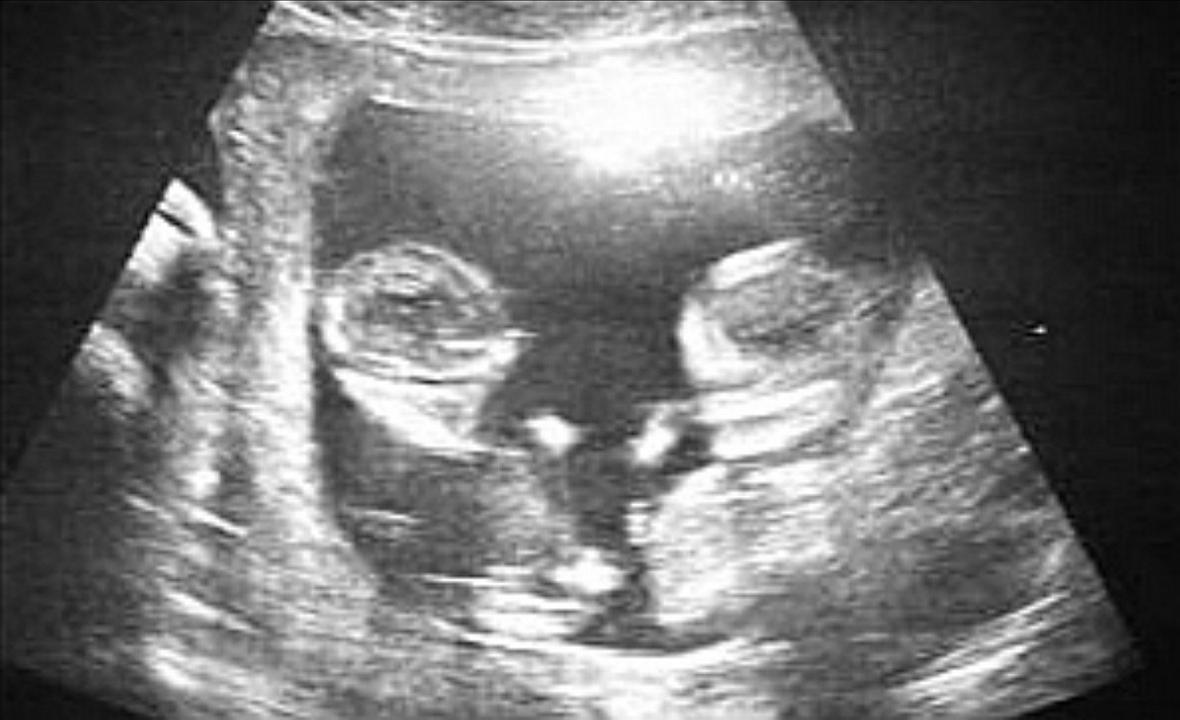

当时在专家门诊的是刘彩霞医生,在检查过程中,医生发现她的病情非常严重:孕妇51岁高龄,怀的是双胞胎,当时已经是第33周。经询问得知,吕凤琴有近1个月不能平卧,在家里睡不了觉,呼吸困难,血压还高。给刘彩霞医生的第一个印象是,这是个非常高危的孕妇。

护士为吕凤琴做胎心监护,正常的胎儿心率应该在120-160次/分,伴随着母亲心率的变化,胎儿的心率也会随之加快。在20分钟的胎心监护中应该有2-3次胎动。但是,吕凤琴肚子中的胎儿却没有什么变化,莫非,肚子里的胎儿有什么不测吗?